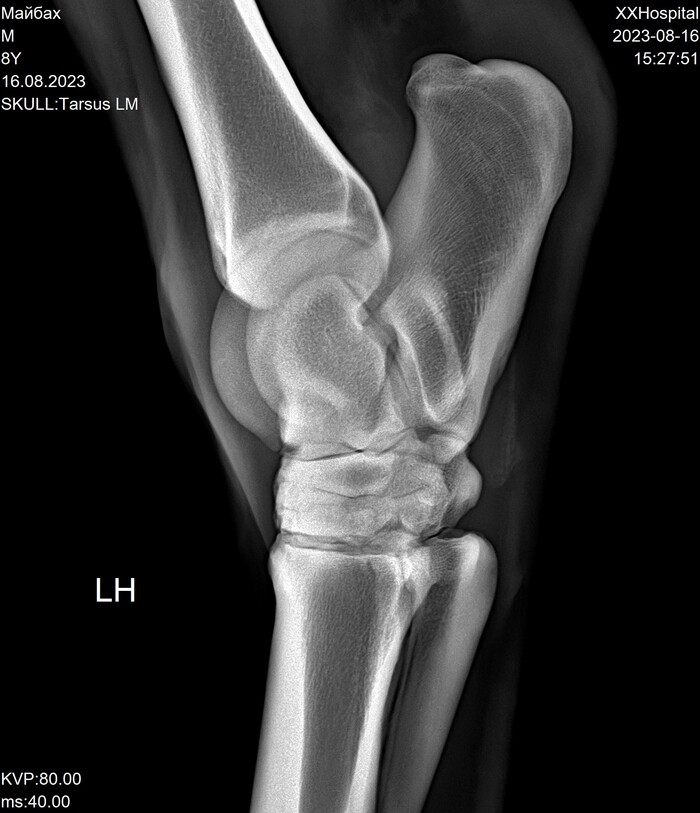

На этих x-ray снимках Домбай.

У него артроз (или артрит, я такой себе врач) пальчиков на руках.

Плюс косточка в копыте подходит очень близко к краю.